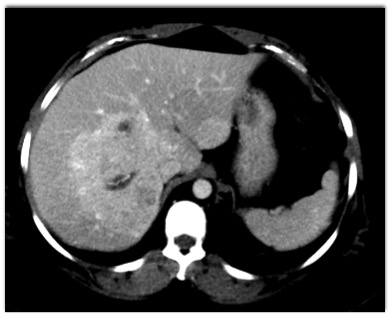

In this 30ish year old female with abdominal pain the most likely diagnosis is?

CTisus Quiz   CTisus Quiz

hemangioma

hepatoma

focal nodular hyperplasia

hepatic adenoma